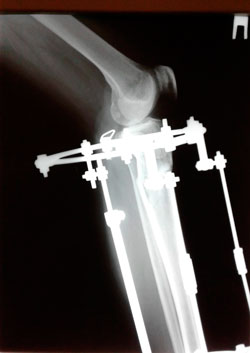

Перед снятием аппаратов

image-13-10-20-06-09-7.jpg

image-13-10-20-06-09-6.jpg

image-13-10-20-06-09-5.jpg